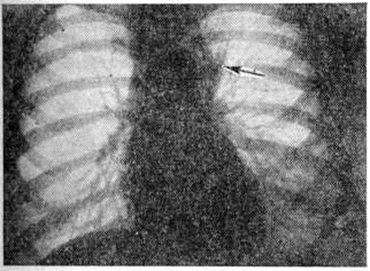

Рис. 8.

Рентгенограмма грудной клетки (прямая проекция) при лимфогранулематозе: определяется умеренное расширение верхних отделов срединной тени, больше влево (указано стрелкой).

При рентгенологическое исследовании органов грудной клетки при Лимфогранулематоз может определяться расширенная срединная тень (рисунок 8), чаще в верхнем и среднем отделах, обусловленная увеличением трахеальных, трахеобронхиальных и бронхопульмональных лимфатических, узлов. В зависимости от поражения различных групп лимфатических, узлов срединная тень может быть симметричной или асимметричной.